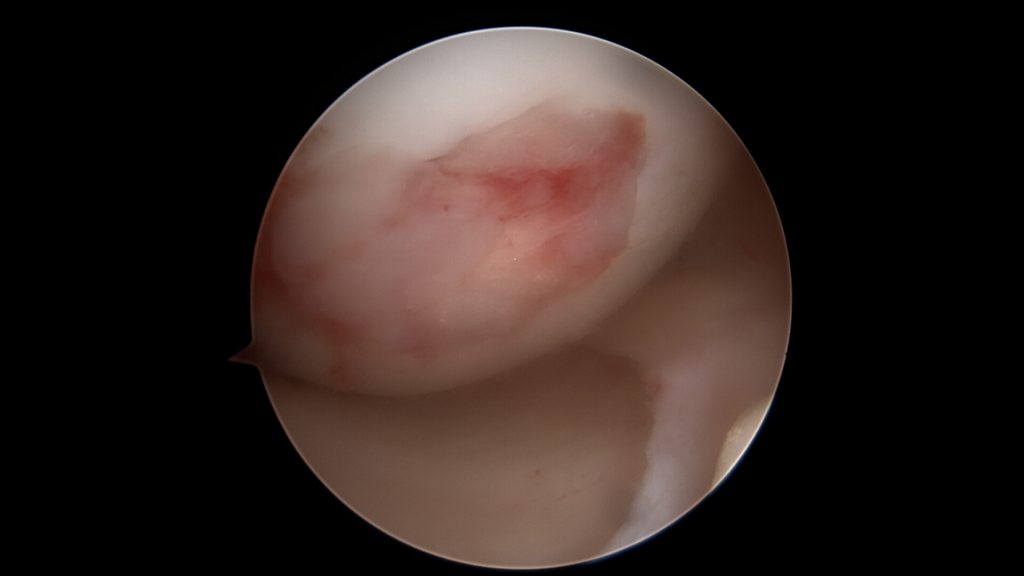

W przypadku niewielkich uszkodzeń czwartego stopnia, punktowych, poniżej 1 cm2, stosuje się odświeżenie dna ubytku. W ten sposób wydostająca się spod chrząstki krew tworzy skrzep wypełniający ubytek. Kiedy jednak jest on większy konieczne jest jego wypełnienie materiałem. Stosuje się preparaty hyaluronowe (np: Hyalofast) lub błony kolagenowe. Są one rusztowaniem dla komórek, które zagnieżdżają się w nich oraz rozpoczynają tworzenie regeneratu chrząstki stawowej.